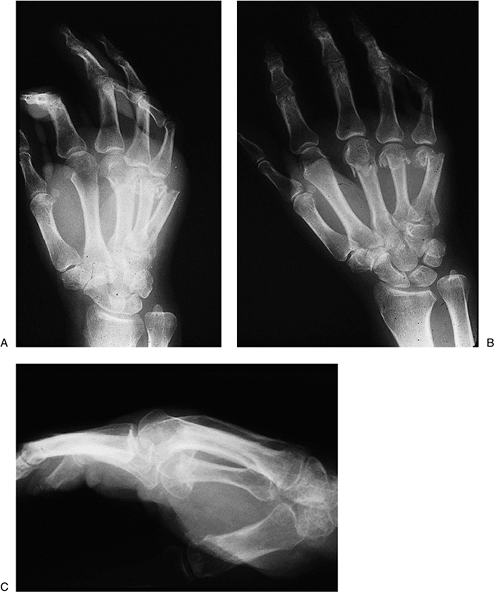

Figure 9-20 X-ray appearance of Bennett’s fracture with K-wire fixation. A, B. Prereduction appearance. C, D.

Note the anatomic reduction and K-wire fixation of the fracture

fragment, and a second transarticular K-wire across the CMC joint. Question

to the reader: What would you have done differently in terms of the cut

off ends of the K-wires? Answer: A 90-degree bend prior to cutting off

the K-wires would have prevented migration of the ends of the pins

beneath the dorsal cortex of the metacarpal and made pin removal at 6

weeks a less complex procedure. -

Figure 9-20 demonstrates the x-ray appearance of a Bennett’s fracture and its reduction and fixation with K-wires.